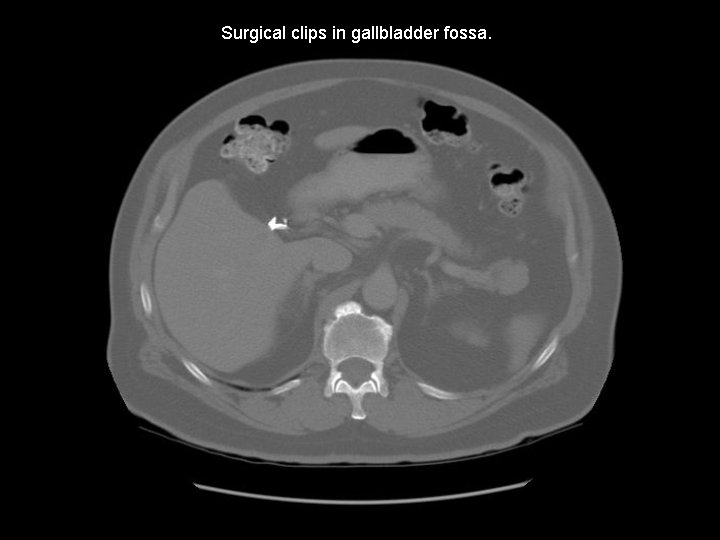

Surgical clips in gallbladder fossa.